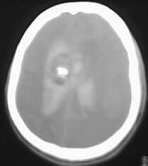

男39岁,今天早上1点多发病,来医院时病人已经昏迷.ct示脑室内出血在侧脑室顶部示有片状钙化

侧脑室扩大,脑室内大量出血,脑室内肿块阴影并钙化,脉络膜乳头状瘤继发出血可能。

右侧侧脑室室间孔区肿块,内有大片钙化,双侧侧脑室出血、脑室铸形,考虑中枢神经细胞瘤合并出血。